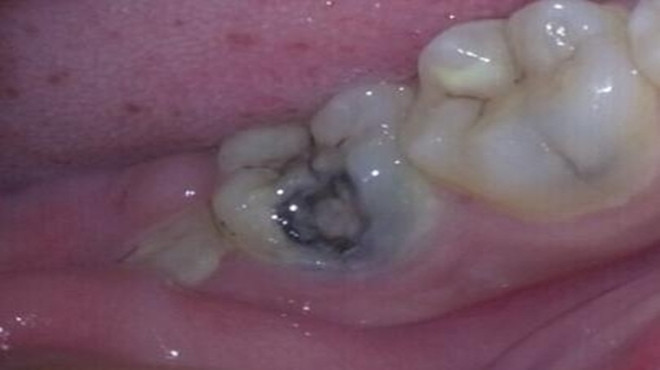

蛀牙严重后会伤害到牙髓,到时候就会引发牙髓炎、根尖周炎等感染疾病,治疗起来就会更加的费事了,需要的时间与金钱也会增加很多。

蛀牙会带来疼痛,平时可能没啥感觉,但是只要一吃食物牙齿就会疼的厉害,久而久之就会造成偏嚼的习惯,让整个面部看起来都不协调,而且蛀牙如果发生在前牙,张口就是一个黑洞,那该多难看啊。